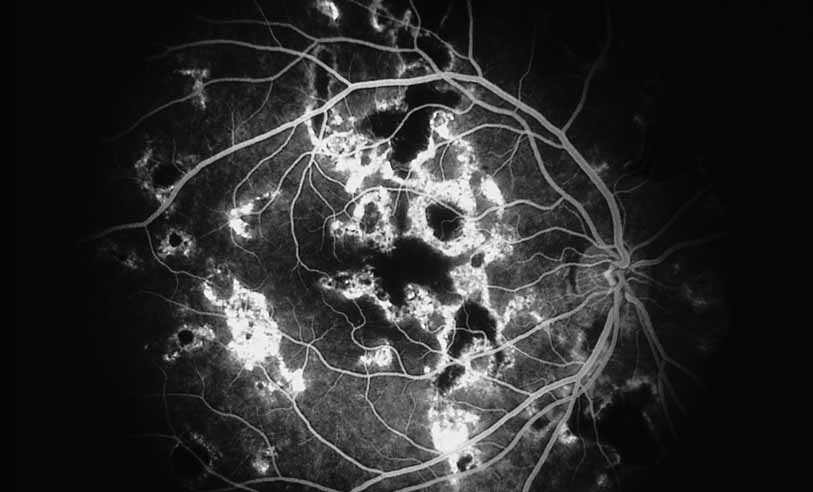

A third instance in which fluorescein angiography concentrating on the optic nerve may be helpful is in eyes with vascular engorgement of the optic nerve, especially with media opacities. Fluorescein angiography may help the clinician distinguish abnormally leaking capillaries from neovascularization. In acute multifocal hemorrhagic retinal vasculitis, optic nerve involvement is common in the early stages of the disease, 47 with optic nerve disc neovascularization seen later (see Figs. 10, 11, 12, and 13). Another fluorescein angiographic clue to the distinction between optic disc vessel engorgement and true neovascularization is the presence of associated large zones of retinal capillary nonperfusion such as those seen in sarcoidosis (see Figs. 14 and 15),34–40 acute multifocal hemorrhagic retinal vasculitis (see Figs. 10 and 11),47 or Eale disease (see Figs. 16 and 17).48–52

Fig. 12 Acute multifocal hemorrhagic retinal vasculitis. The patient later developed disk neovascularization with vitreous hemorrhage. Note the areas of neovascular leakage from the optic nerve.

Fig. 13 Acute multifocal hemorrhagic retinal vasculitis. The patient underwent scatter laser photocoagulation to the zones of retinal capillary nonperfusion, which resulted in regression of the neovascularization.